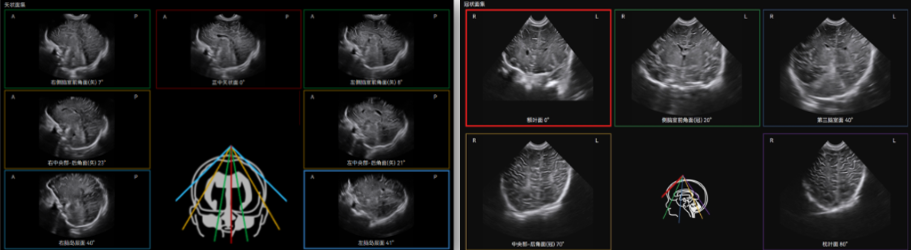

Craniocerebral Ultrasound Tomography (Infant) significantly simplifies the examination by automatically identifying and displaying the 12 standard craniocerebral sections.